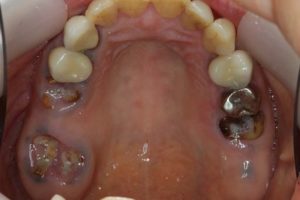

どのように変わったか、下の写真をご覧ください。

銀歯が多かったのですべて昔の銀歯の下もちりょうしながらセラミックにかえることができてとても満足しています。やっぱり白い歯よいですね。

治療お疲れ様でした。たくさん銀歯が入っていたのですが、最後には真っ白になりましたね。銀歯をやり直す材料にはセラミックとプラスティックがあるのですが、基本的にできるだけプラスティックで治すようにしています。この患者さんも、可能な限りプラスティックで治し、どうしても無理なところだけセラミックにしました。そのため歯を削る量が少ないことに加え、費用もかなり抑えることができます。たくさん治しましたが、全部セラミックで治さなければならないとなっていたら、もっともっと時間も費用もかかっていたかもしれません。当院では、初診時に治療方針や期間や費用などを1時間ほどかけて詳しく説明していますので、患者さんには治療内容について十分納得していただいていると考えています。「親身になって治療してくれる」とおっしゃっていただいたことは、そういったところを評価して頂いたのではいかと思っております。